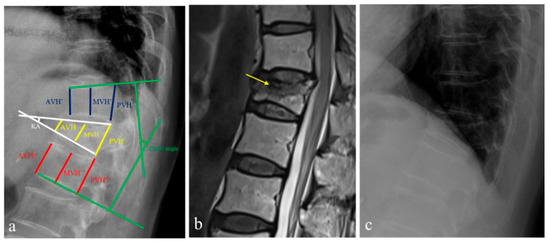

- Sadiqi, S.; Verlaan, J.J.; Lehr, A.M.; Chapman, J.R.; Dvorak, M.F.; Kandziora, F.; Rajasekaran, S.; Schnake, K.J.; Vaccaro, A.R.; Oner, F.C. Measurement of kyphosis and vertebral body height loss in traumatic spine fractures: An international study. Eur. Spine J. 2017, 26, 1483–1491. [Google Scholar] [CrossRef] [PubMed]

- Keynan, O.; Fisher, C.G.; Vaccaro, A.; Fehlings, M.G.; Oner, F.C.; Dietz, J.; Kwon, B.; Rampersaud, R.; Bono, C.; France, J.; et al. Radiographic measurement parameters in thoracolumbar fractures: A systematic review and consensus statement of the spine trauma study group. Spine 2006, 31, E156–E165. [Google Scholar] [CrossRef]

- Hsu, W.E.; Su, K.C.; Chen, K.H.; Pan, C.C.; Lu, W.H.; Lee, C.H. The Evaluation of Different Radiological Measurement Parameters of the Degree of Collapse of the Vertebral Body in Vertebral Compression Fractures. Appl. Bionics Biomech. 2019, 4021640. [Google Scholar] [CrossRef]